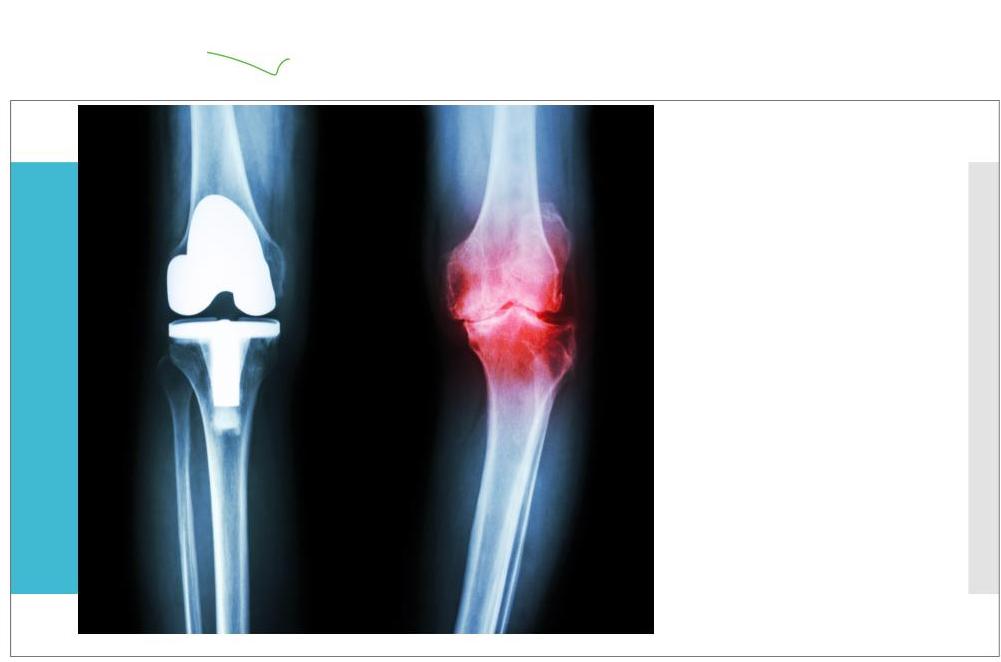

Surgical joint replacement